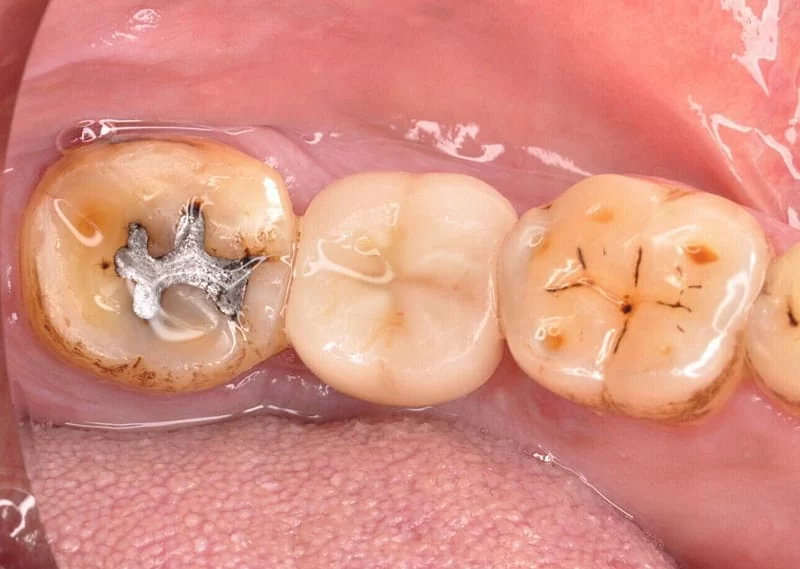

植牙前 <圖二>

植牙第一階段 <圖三>